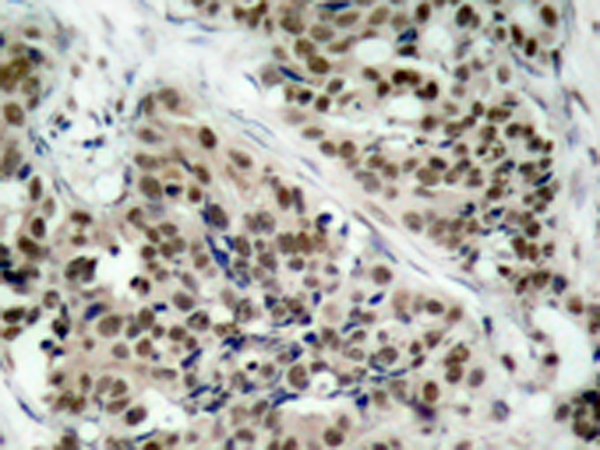

IHC positive control:

Human breast carcinoma

IHC Recommend dilution:

50-100